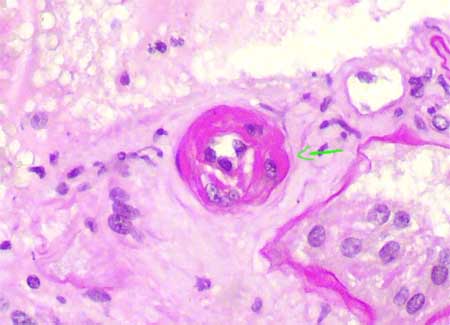

Las lesiones arteriolares son las más características: cambio hialino nodular en la media y hacia la adventicia; pueden verse pequeños nódulos reemplazando células individuales. En ocasiones se ven como múltiples nódulos pequeños con un aspecto que se ha descrito como "en collar de perlas". La hialinosis arteriolar de la hipertensión y/o arterioesclerosis suele ser menos nodular y se ubica principalmente en el espacio subendotelial o intimal. Aunque muy sugerentes de toxicidad crónica por ciclosporina, estas lesiones no son tampoco específicas; además, muchos autores utilizan criterios morfológicos diferentes para diagnosticar toxicidad crónica, esta es una de las principales razones para la gran variabilidad en la incidencia de la toxicidad por ACN de acuerdo a diferentes centros; por ejemplo, en los trabajos de Nankivell et al. (Transplantation. 2004 Aug 27;78(4):557-65; [PubMed link]; N Engl J Med. 2003 Dec 11;349(24):2326-33 [PubMed link][Free full text]) encuentran toxicidad crónica por ciclosporina en casi el 100% de trasplantados renales recibiendo el medicamento, ellos utilizan como único criterio para diagnosticarla, la presencia de depósitos hialinos arteriolares formados después del trasplante (estudian biopsias del donante), no importando su localización ni sus características, un punto de vista cuestionable.

Figura 19. Aunque para algunos autores los signos arteriolares de toxicidad crónica por anticalcineurínicos (ACN) consisten en depósitos hialinos de cualquier tipo, para otros es muy importante la carcaterística nodular de estos depósitos, remplazando áreas de la media muscular o proyectándose hacia la adventicia (flechas). Los depósitos subendoteliales pueden verse, con mucha frecuencia, en pacientes hipertensos o diabéticos no recibiendo ACN y son, por lo tanto, aun más inespecíficos. (PAS, X300).

Figura 20. Observe los pequeños depósitos hialinos que ocupan la media o proyectan hacia la deventicia (flechas); este hallazgo es muy sugerente de toxicidad crónica por ciclosporina. Debemos observar también fibrosis en banda y descartar otras alteraciones que puedan producir disfunción crónica del injerto. (Tricrómico de Masson, X400).

Figura 21. Aunque en esta arteriola los depósitos hialinos reemplazan casi toda su pared, la característica nodular de ellos, protruyendo hacia la adventicia, es sugerente de toxicidad por ACN. (PAS, X400).